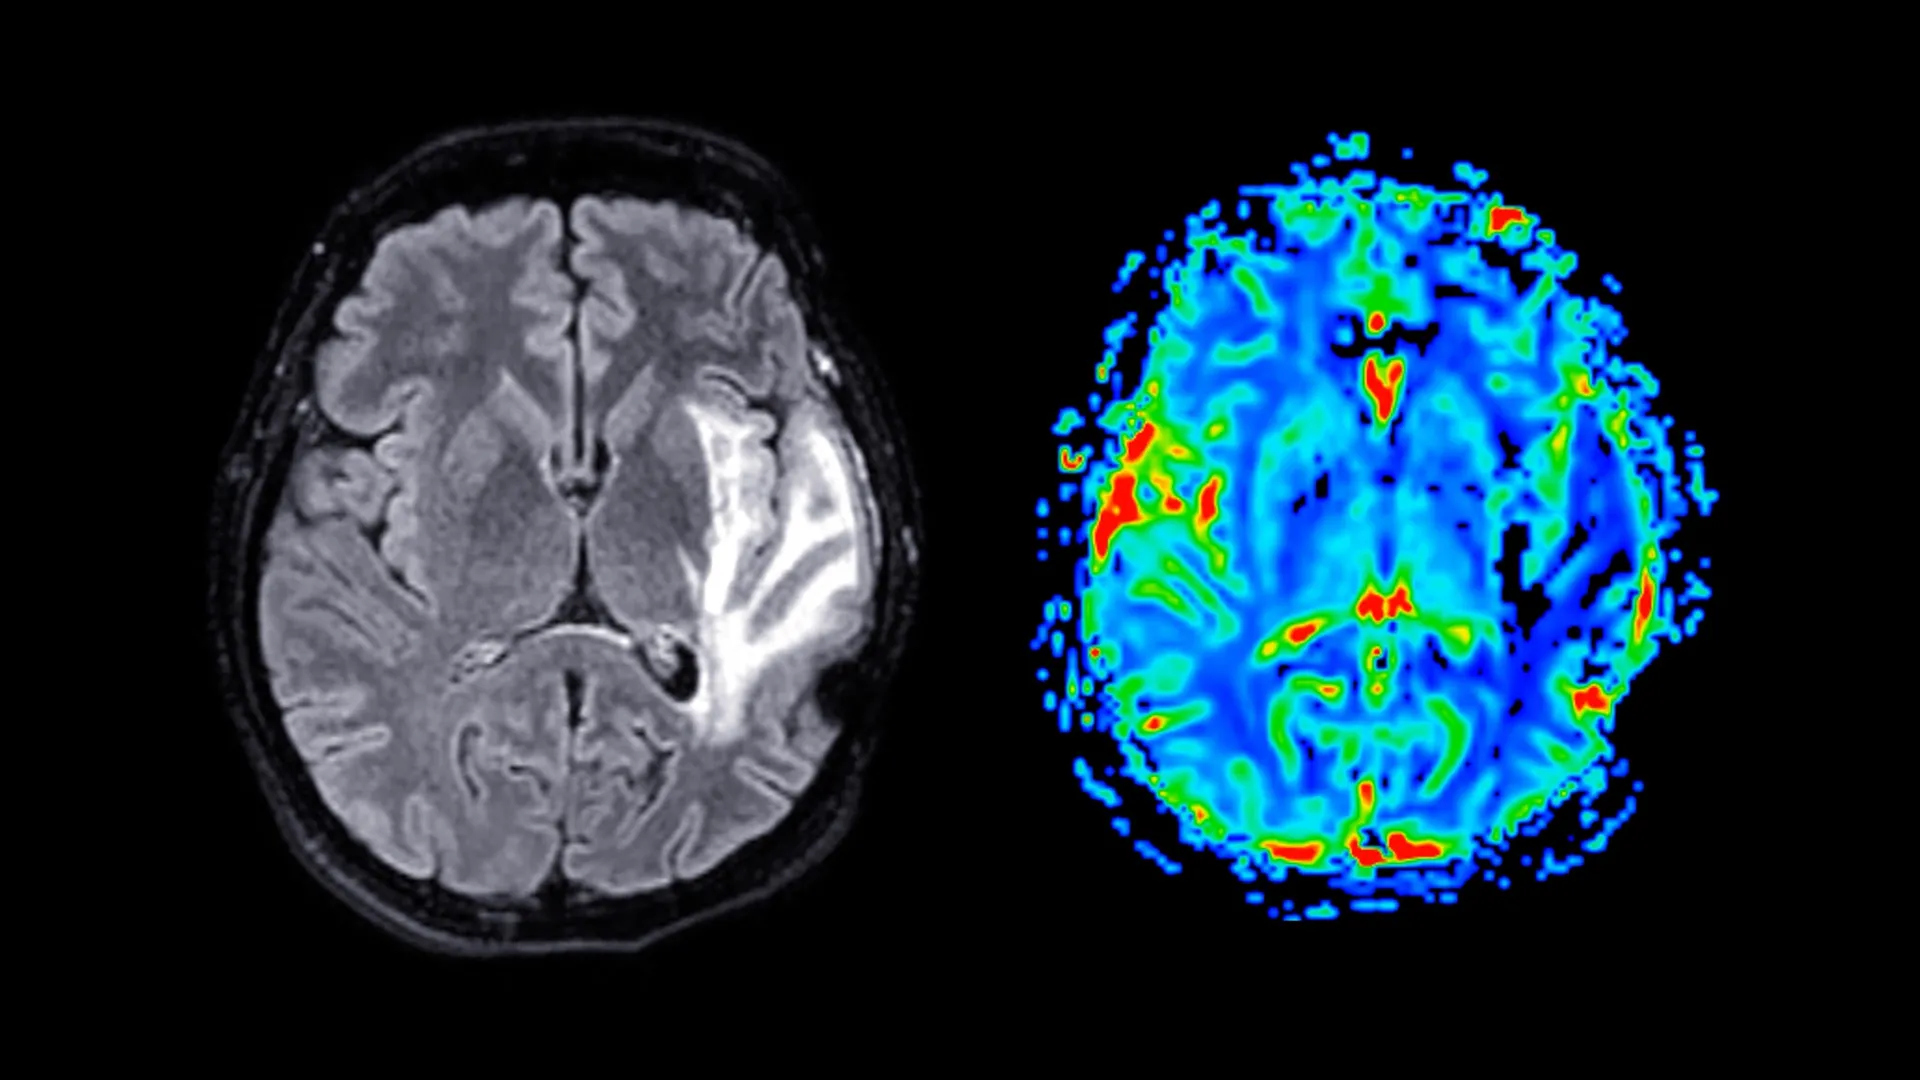

Participants engaged in the completion of detailed questionnaires designed to capture information regarding menopausal symptoms, psychological health status, established sleep patterns, and general health indices. A subset of these individuals also underwent cognitive assessments designed to evaluate memory capabilities and response times. Furthermore, approximately 11,000 women were subjected to magnetic resonance imaging (MRI) scans, enabling the researchers to meticulously examine structural differences within the brain. The average age at which menopause was attained among the study participants was approximately 49.5 years. Women who were prescribed HRT typically initiated treatment around the age of 49.

Neuroimaging data revealed that post-menopausal women exhibited substantial reductions in grey matter volume, an observation that held true regardless of their HRT status. Grey matter, the primary component of the central nervous system, is comprised of neuronal cell bodies and plays a crucial role in a myriad of cognitive functions, including information processing, the orchestration of motor control, and the intricate regulation of memory and emotional responses. The brain regions most significantly affected by these structural alterations included the hippocampus, a structure vital for the formation and consolidation of memories; the entorhinal cortex, which serves as a critical conduit for information transfer between the hippocampus and other brain regions; and the anterior cingulate cortex, a region integral to emotional regulation, decision-making processes, and the maintenance of focused attention.

Professor Barbara Sahakian, the senior author of the study from the Department of Psychiatry, offered further insight into the potential long-term implications of these findings, suggesting, "The specific brain regions identified as exhibiting these structural differences are precisely those that are characteristically impacted by Alzheimer’s disease. Menopause may, therefore, render these women more susceptible to neurodegenerative conditions later in life. While not a singular determinant, this observation could contribute to understanding the observed phenomenon of nearly twice as many dementia cases occurring in women compared to men."